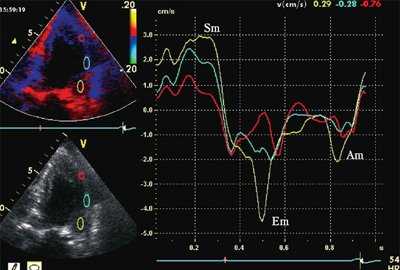

ЭхоКГ (стандартная и в режиме тканевой допплерографии) проводилась на ультразвуковой диагностической системе Vivid Five фирмы General Electric (США) секторным датчиком c частотой 3,75 МГц. Исследовалось движение продольных волокон миокарда в проекциях по длинной оси левого желудочка из верхушечного доступа. Тканевая допплерография проводилась в 4-, 3- и 2-камерной проекциях в каждом из 16 сегментов левого желудочка и в 4 точках митрального кольца: у основания заднеперегородочной, боковой, нижней и передней стенок левого желудочка. Оценивались следующие параметры.

- Пиковые миокардиальные скорости: Sm (см/с) - пиковая систолическая скорость; Em (см/с) - пиковая скорость раннего диастолического расслабления; Am (см/с) - пиковая скорость в фазу систолы предсердий.

Оценивались также показатели тканевой допплерографии, характеризующие феномен ПСУ.

- Амплитуда постсистолического пика скорости, регистрируемого в фазу изоволюмического расслабления (Sps). Вычислялось отношение скоростей Sps/Sm.

- Форма кривой движения миокарда в течение сердечного цикла. Формы кривых движения миокарда в зависимости от наличия ПСУ подразделялись на 3 типа: "норма", "ступень" и "седло".

На рис. 3-5 приведены различные варианты ПСУ у больных с постинфарктным кардиосклерозом.

![Тканевая допплерография в норме. У больного с постинфарктным кардиосклерозом регистрируется высокоамплитудный пик постсистолической скорости (Sps)]()

![Тканевая допплерография при постинфарктном кардиосклерозе. У больного с постинфарктным кардиосклерозом регистрируется высокоамплитудный пик постсистолической скорости (Sps)]()

б) При постинфарктном кардиосклерозе. У больного с регистрируется высокоамплитудный пик постсистолической скорости (Sps).

Вертикальная линия (AV) на рис. 3-5 соответствует времени закрытия аортального клапана. На представленных графиках также отмечается наличие базально-верхушечного градиента (снижение пиковых миокардиальных скоростей, продольного систолического смещения и деформации от основания к верхушке левого желудочка).

Достоверных различий между гипо- и акинетичными сегментами по характеристикам ПСУ не было выявлено, хотя в подгруппе акинетичных сегментов ПСУ регистрировалось несколько чаще. В нормокинетичных сегментах у больных с постинфарктным кардиосклерозом пики Sps и STps определялись значительно чаще, чем в контрольной группе (53 и 30% в сравнении с 18 и 2% случаев соответственно; p<0,05). ПСУ также было выявлено в 68% точек митрального кольца, расположенных у основания стенок левого желудочка с нарушенной сократимостью.